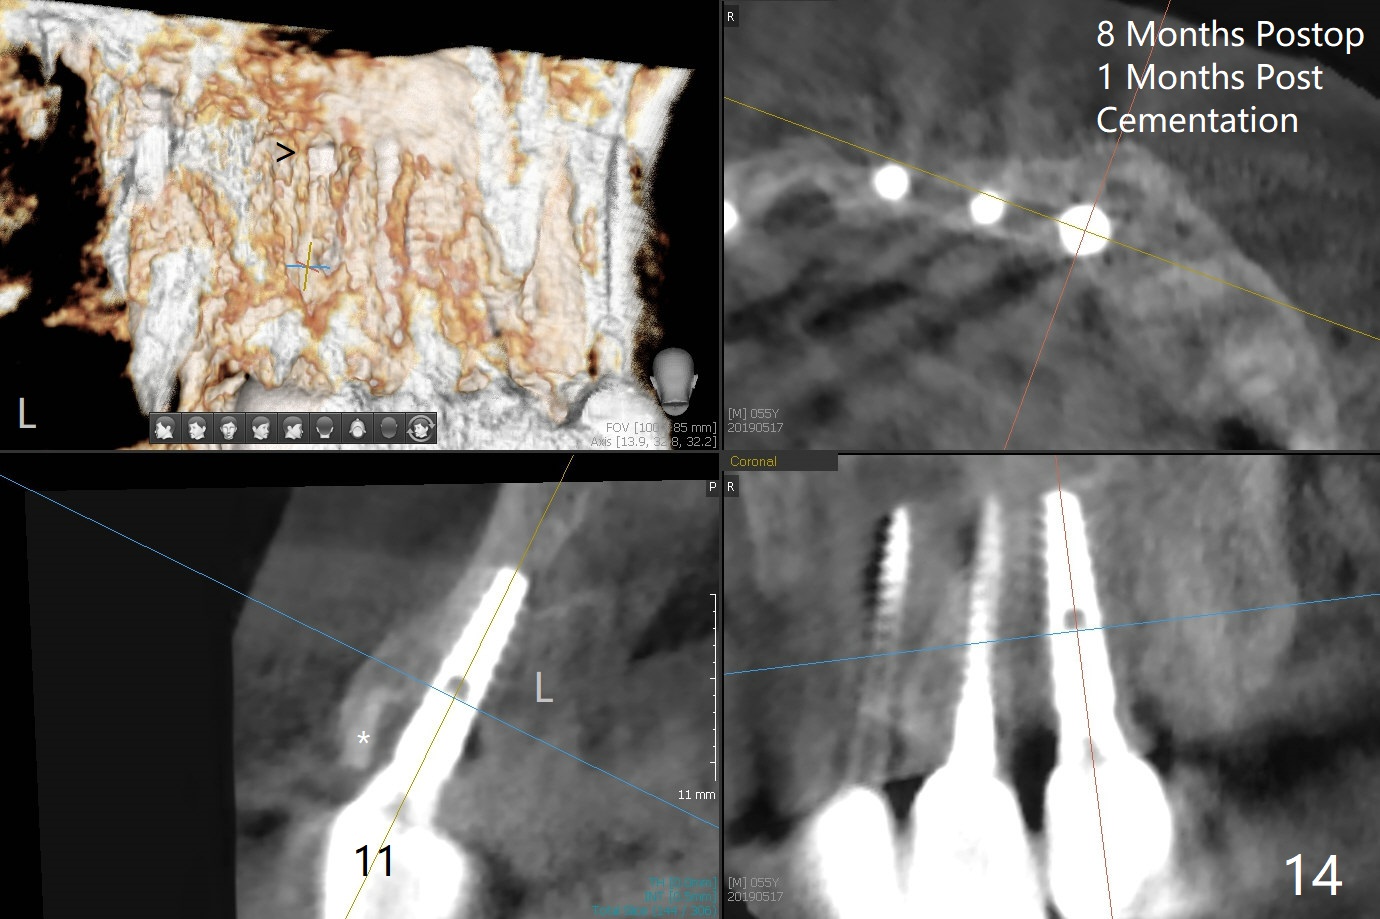

The buccal plate at #10 undergoes atrophy 9 months post immediate implant (Fig.1 *). To prevent the same post-extraction complication at #11, a technique called socket shield is going to be adopted. The buccal portion of the root (Fig.2-6 R, half-moon shaped) remains in place while a 3.5x13 mm implant is placed in the palatal portion of the socket (>50 Ncm). In fact the root is trimmed slightly subcrestal (Fig.6 C). It is assumed that there will be no or minimal bone resorption as long as the periosteum between the buccal plate and the remaining buccal root is not disturbed after tooth removal. After placement of a 4.5x15 degrees A (2mm) angled abutment and Vanilla graft (Fig.7 *), an immediate provisional is fabricated (using a central incisor crown form for #10 because of extra wide space of #11, Fig.8). There is no buccal plate atrophy at the canine 11 days postop (Fig.9). There is smooth transition from the grafted bone to the native bone 4.5 months postop (Fig.10). The buccal plate remains non-atrophic at the canine 4.5 months postop (Fig.11,12). CT taken 1 month post cementation shows that the implants at #10 and 11 are placed somewhat lingually (Fig.13,14 L (*: socket shield)). Gingival swelling is noted (Fig.15 *) with +Bleeding On Probing (^) 8 months post cementation (at the time of #21/24 impression). It appears that the socket shield (Fig.16 S) causes infection and loss of bone graft (*). The shield will be removed with an oblique accessory incision to save the papilla between #10 and 11 (Fig.17 black line). Prepare PRF for sticky bone (x1).